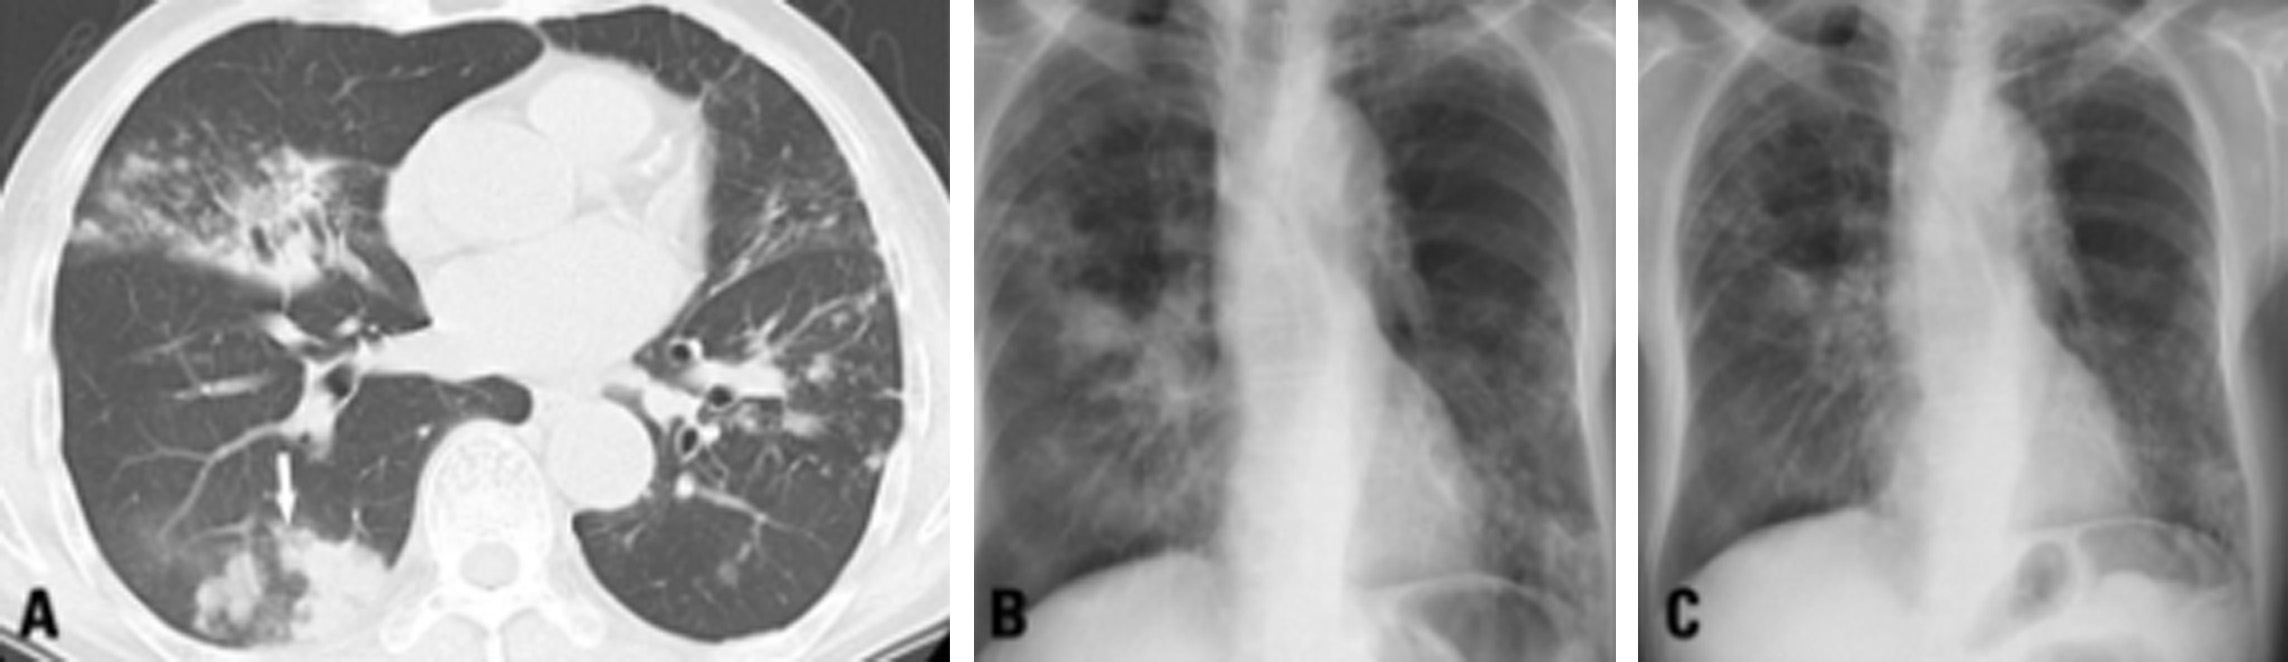

Lady windermere syndrome treatment. Complex or MAC which are present in soil and water. Treatment with thoracoscopic lobectomysegmentectomy for right middle lobe and lingular bronchiectasis associated with non-tuberculous mycobacterial disease. This case illustrates the classic chest radiograph and computed tomography findings of The Lady Windermere Syndrome.

Eur J Cardiothorac Surg 40 2011 pp. A lady as described in literature is a woman of good social standing and has a polite and refined disposition. The radiographic findings are bronchiectasis and small nodules predominately located within the middle lobe and lingula. These organisms enter hosts via the gastrointestinal tract or the lungs. Lady Windermere syndrome Ann Marie Kumfer MD Hawa Edriss MD AbstrAct Non-tuberculosis Mycobacterium spp NTM pulmonary disease is increasing in incidence and is a common cause of undiagnosed lung disease in older patients. Dr Surya Bhatt 801 Ostrum Street Bethlehem Pennsylvania USA 18015 Tel. Treatment with thoracoscopic lobectomysegmentectomy for right middle lobe and lingular bronchiectasis associated with non-tuberculous mycobacterial disease. Lady Windermeres Syndrome In 1992 two physicians published a medical article describing six older women with infection of their lungs by the germ Mycobacterium avium. The Lady Windermere syndrome.